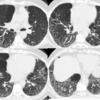

Honeycomb CT 4in1

Date: 01/06/2012

Views: 3187